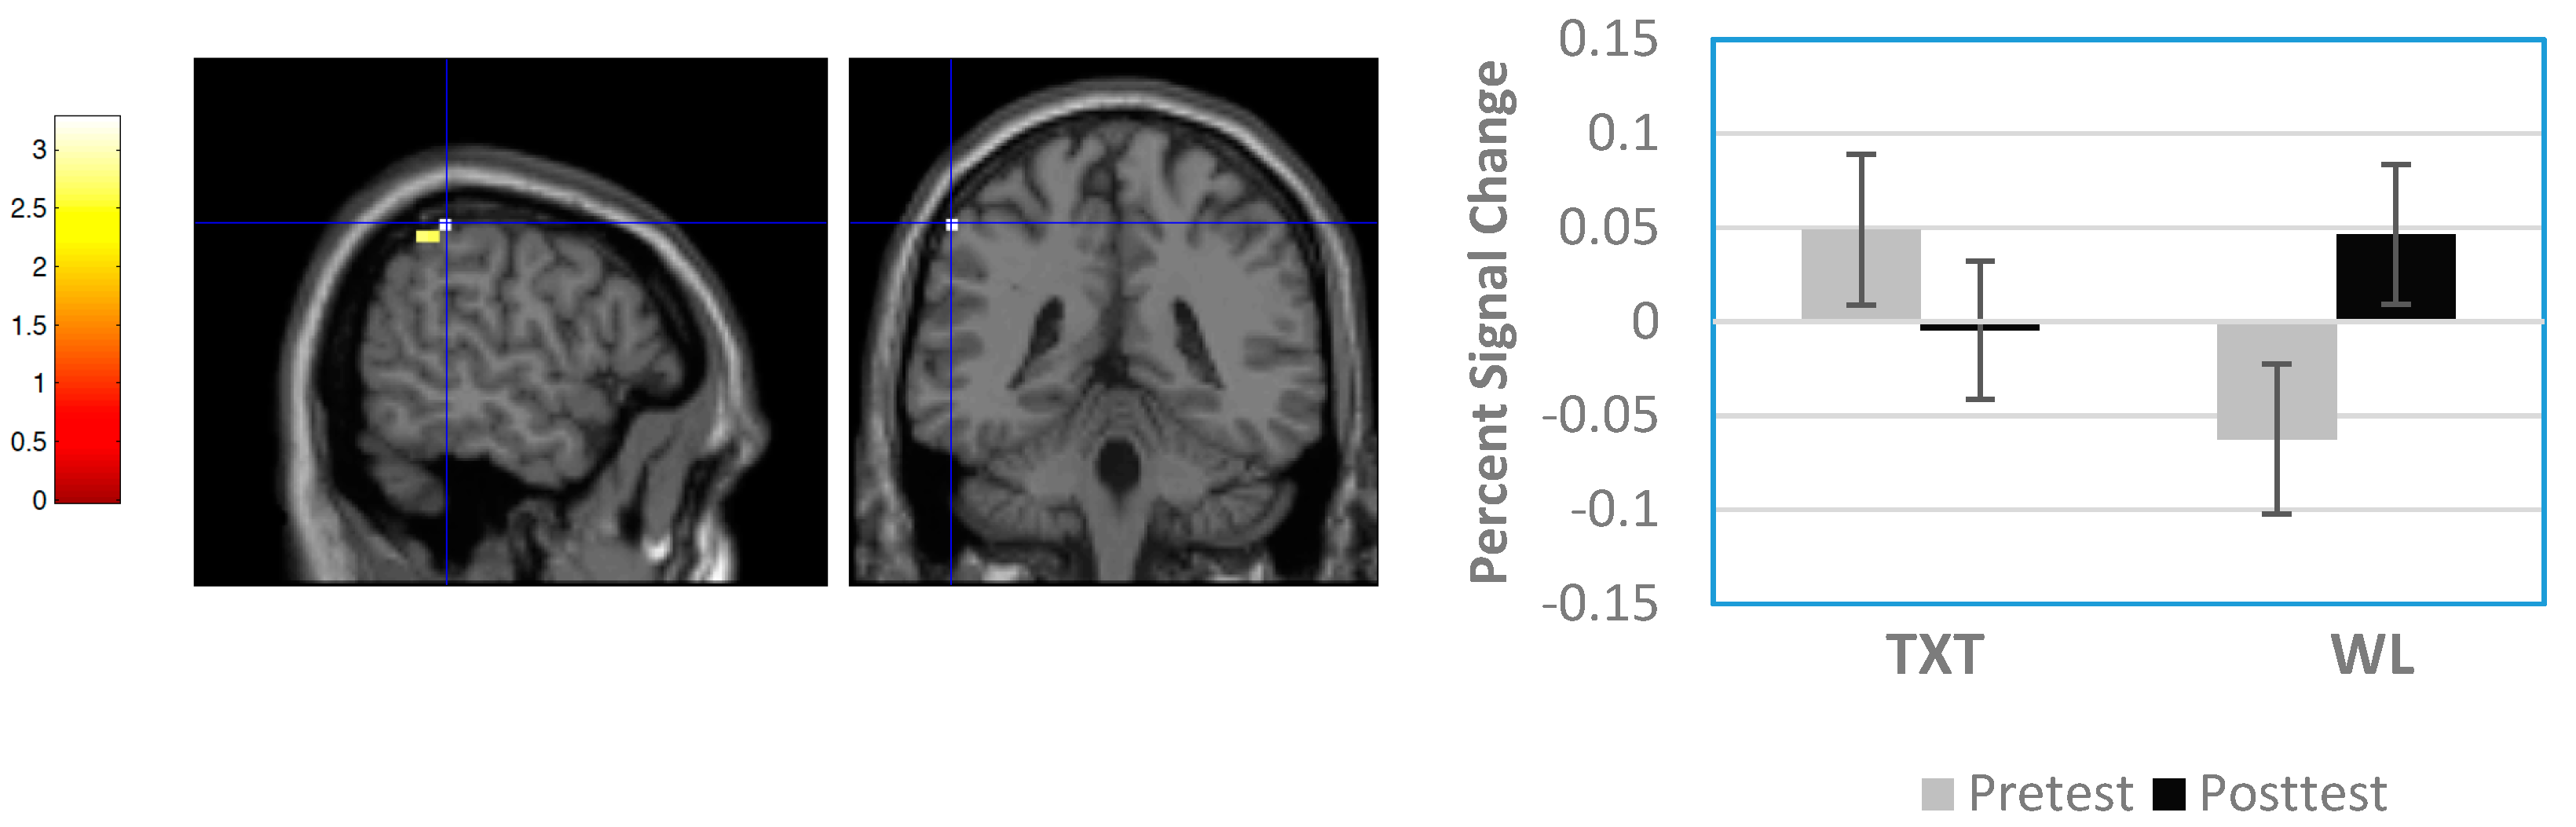

3.3.1. Whole Brain Results

3.3.2. Region-of-Interest Results

| Waitlist > Treatment | Right medial frontal gyrus | 8 | 8 | 24 | 52 | 2.54 | 0.350 | 0.006 | 12 |

| Left frontal subgyral | WM | −24 | 0 | 32 | 2.64 | 0.350 | 0.004 | 15 | |

| Right cingulate gyrus | 32 | 16 | 20 | 28 | 2.85 | 0.350 | 0.002 | 30 | |

| Left cingulate gyrus | 24 | −12 | −16 | 40 | 2.78 | 0.350 | 0.003 | 12 | |

| Right putamen | 24 | 20 | −16 | 2.99 | 0.350 | 0.001 | 21 | ||

| Right superior temporal gyrus | 22 | 56 | −56 | 16 | 3.19 | 0.350 | 0.001 | 10 | |

| Group X Time Interactions | |||||||||

| Right superior frontal gyrus | 6 | 16 | 12 | 56 | 2.75 | 0.677 | 0.003 | 26 | |

| Left middle frontal gyrus | 46 | −48 | 40 | 16 | 2.58 | 0.677 | 0.005 | 14 | |

| Left inferior parietal lobule | 40 | −56 | −40 | 52 | 2.84 | 0.677 | 0.002 | 17 | |